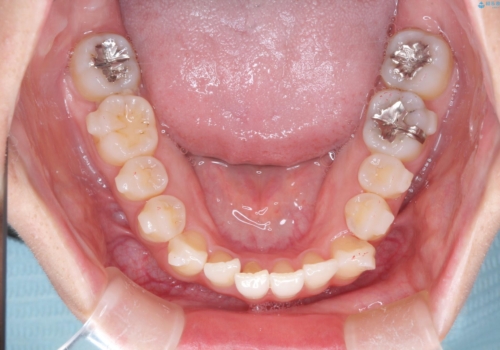

【インビザライン】前歯の凸凹をなおしたい

- 前歯の凸凹を主訴に来院されました。

上顎の急速拡大を行なったのちインビザラインにて治療を行なっております。

今回のケースは後戻りのリスクを低くし、またディスキング量を減らすために上顎の急速拡大を行なっております。